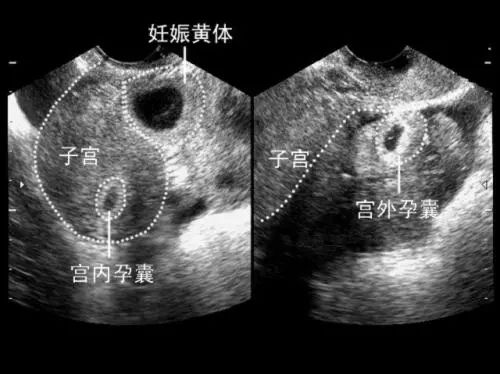

确定是否怀孕,观察妊娠囊、胚胎的大小、数目、位置,判断是单胎还是多胎妊娠。观察胚胎情况,有无胎心搏动,是否有胚胎停止发育。测量头臀长明确孕周,推算预产期。还有重要的一点是排除宫外孕和葡萄胎,看看子宫卵巢有没有异常。